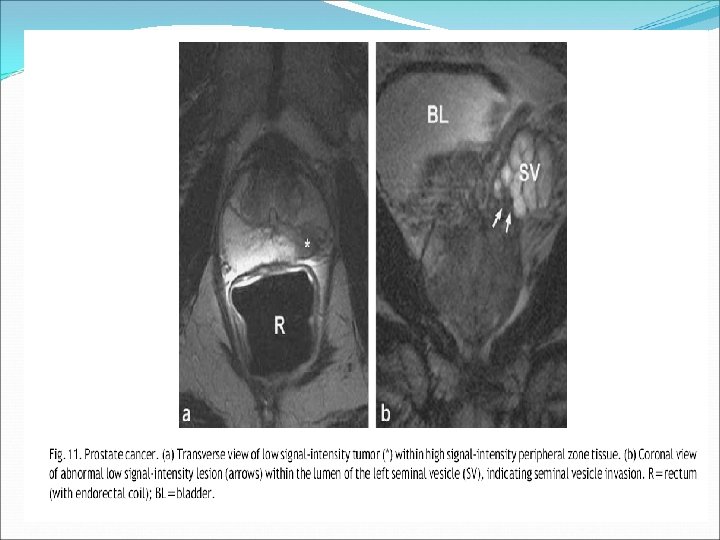

Evaluation of MR Images in Prostate Carcinoma usually from PZ – appear as hypointense lesion. Extracapsular extension : irregular bulging of the prostatic outline, breach of the capsule with extracapsular spread, asymmetry of the neurovascular bundles, and loss of the rectoprostatic angle. Invasion of seminal vesicles ‐ Contiguous areas of low signal intensity extending into the seminal vesicles from the base of the prostate (Note – this also may be seen postradiotherapy & post‐biopsy) Invasion of bladder/rectum Lymph nodes – lymph nodes >1 cm considered involved